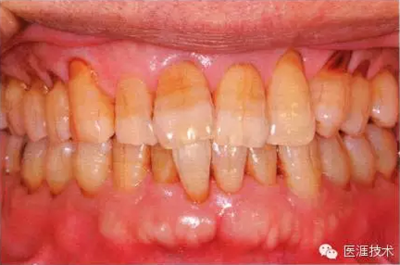

44歲牙周炎女性的臨床照片

44歲患有糖尿病病史(未治愈)。菌斑控制不良。通過牙周探診,全頜有4~8mm的牙周袋,在X光片中可以看到上頜前牙處中度牙槽骨吸收,磨牙處重度牙槽骨吸收。二次齲齒和根面齲齒也有發(fā)生。可以看到浮腫性腫脹,收到刺激后會出血。